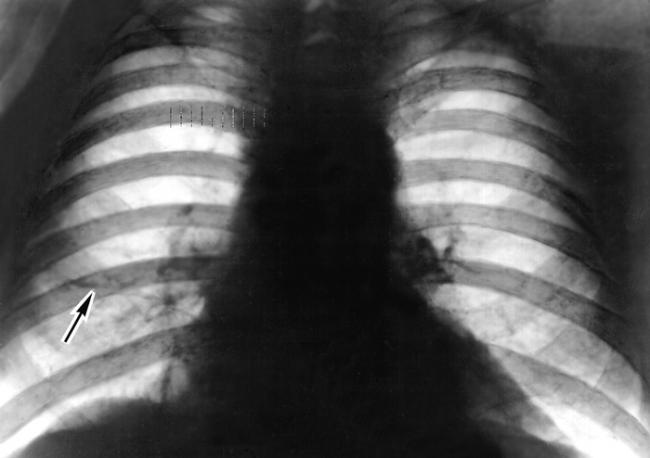

Определить ателектаз при помощи рентгеновских лучей удаётся лишь в редких случаях, именно когда он достаточно обширен и глубок, чтобы дать заметную тень на экране или на фотографической пластинке.

Помимо опроса и объективного осмотра, включающего перкуссию и аускультацию грудной клетки, проводят рентгенологическое исследование в двух положениях тела (в 2-х проекциях). Это основной метод обнаружения ателектазов легких.

На рентгеновских снимках выявляют следующие признаки, указывающие на спадение легочной ткани:

Однородное затемнение в области поражения. Размеры тени зависят от вида ателектаза: при долевом выявляется обширное затемнение, при сегментарном — в виде клина или треугольника, расположенного вершиной к корню легкого, дольковые ателектазы множественные и похожи на очаговую пневмонию. Дистензионный ателектаз расположен низко, около диафрагмы, имеет небольшие размеры и вид поперечных полос или темных дисков. Смещение органов: при компрессионном ателектазе смещение наблюдается в здоровую сторону, так как на стороне поражения давление больше, при обтурационном, наоборот – смещение будет в сторону ателектаза, так как на стороне поражения нарастает притягивающее отрицательное давление. Подъем купола диафрагмы – это видно по расположению печени.

Помимо всего перечисленного выше, рентгеноскопия, то есть исследование «вживую», позволяет увидеть куда смещаются органы в зависимости от фазы дыхания, кашля. Это является дополнительным признаком ателектаза, помогающим выявить тип болезни.